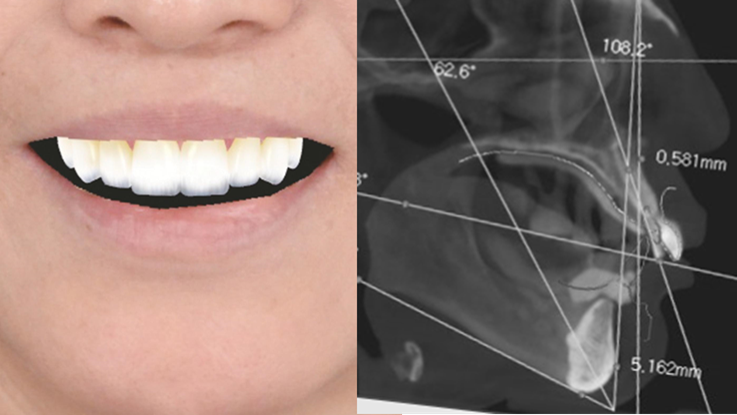

Effective R2STUDIO in complex tooth positioning

- Courtesy of Dr. Jong Cheol Kim, Korea